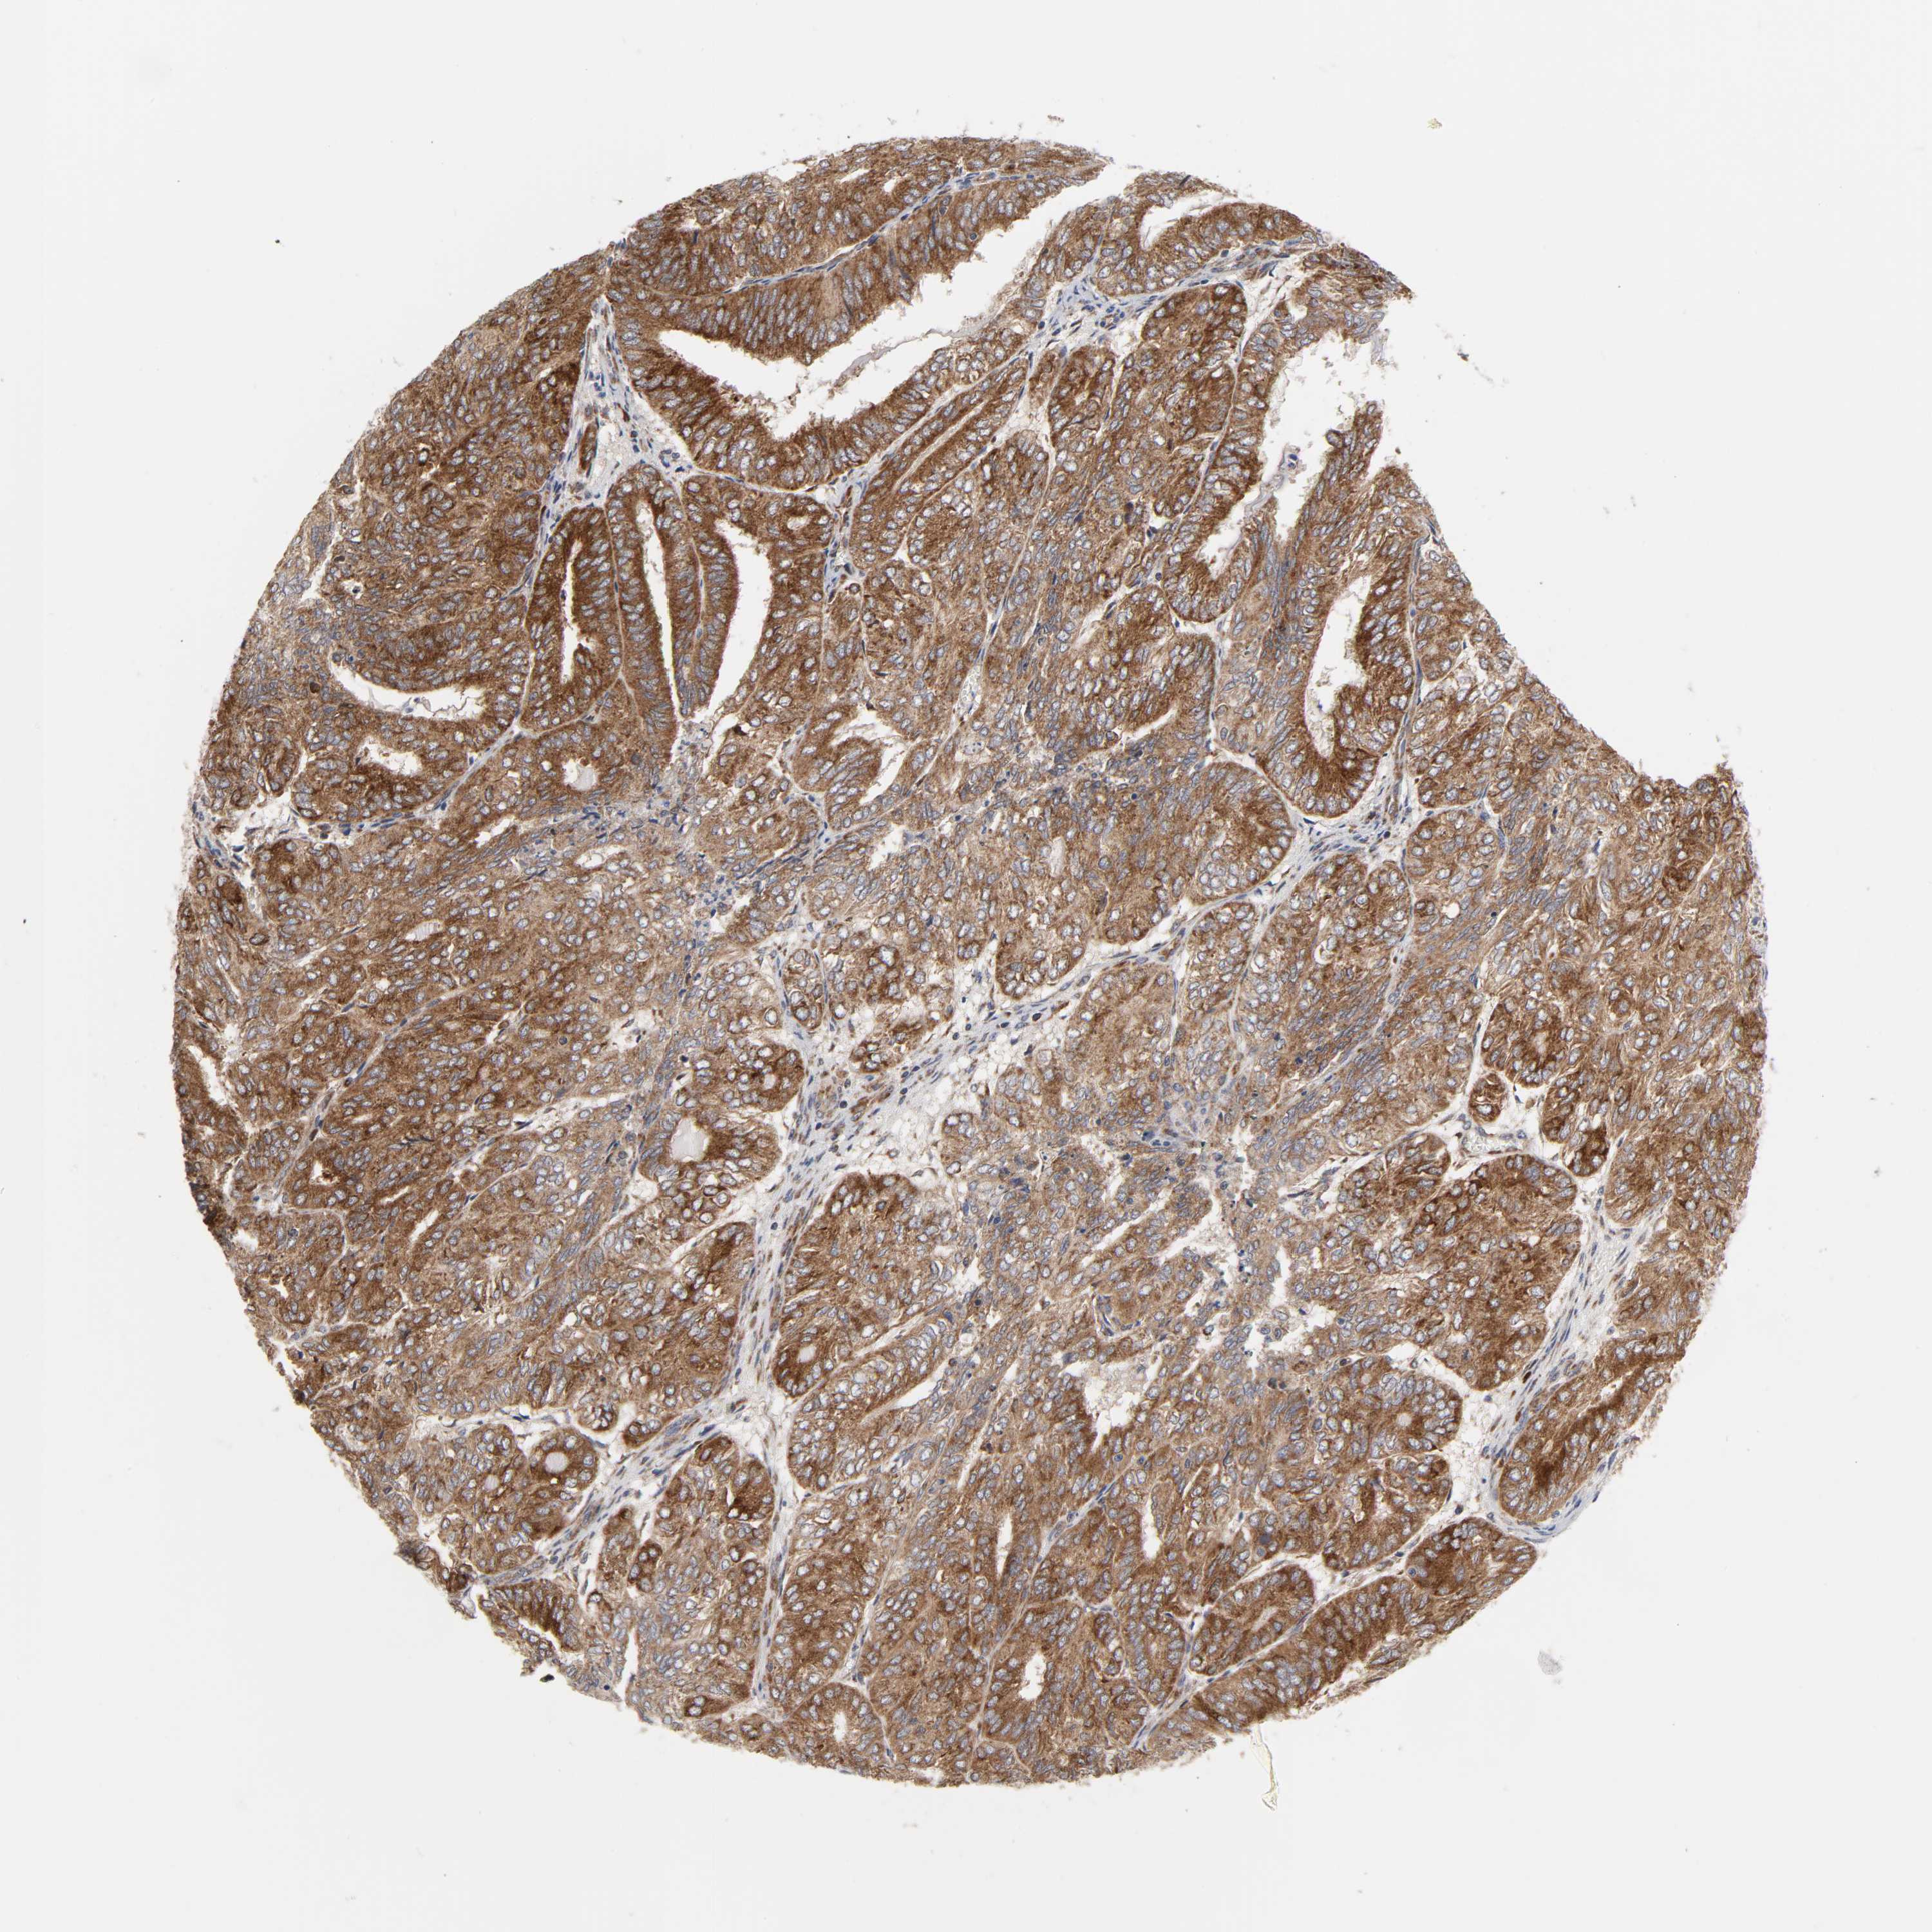

ENDOMETRIAL CANCER - Protein expressioni

A mouse-over function shows sample information and annotation data. Click on an image to view it in a full screen mode. Samples can be filtered based on level of antibody staining by selecting one or several of the following categories: high, medium, low and not detected. The assay and annotation is described here.

Note that samples used for immunohistochemistry by the Human Protein Atlas do not correspond to samples in the TCGA dataset.

Antibody stainingi

Antibody staining in the annotated cell types in the current human tissue is reported as not detected, low, medium, or high, based on conventional immunohistochemistry profiling in selected tissues. This score is based on the combination of the staining intensity and fraction of stained cells.

Each image is clickable and will lead to virtual microscopy that enables deeper exploration of all samples and also displays staining intensity scores, fraction scores and subcellular localization as well as patient and tissue information for each sample.

Antibody HPA027878

Antibody CAB004206

Staining

High

Medium

Low

Not detected

Intensity

Strong

Moderate

Weak

Negative

Quantity

>75%

75%-25%

<25%

None

Location

Nuclear

Cytoplasmic/membranous

Cytoplasmic/membranous,nuclear

Adenocarcinoma, NOS

Adenocarcinoma, metastatic, NOS

Neoplasm, malignant, NOS